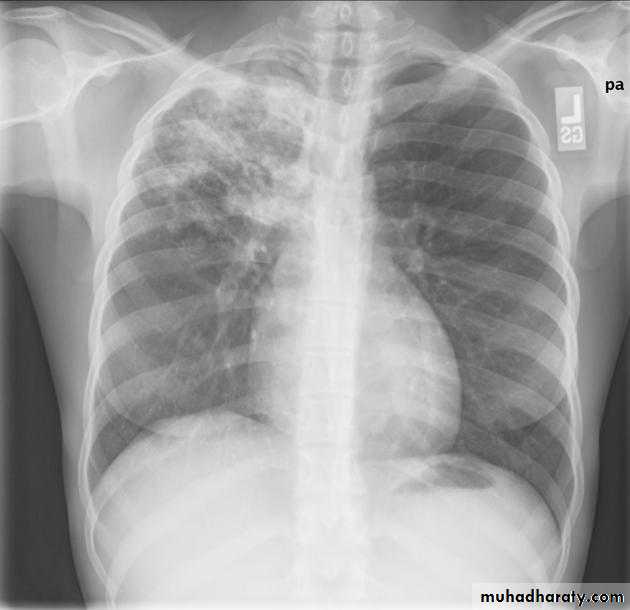

Post primary TB broncho pneumonia cotton wool signBilateral patchy opacities of the upper lobes of the lungs, cotton wool sign.

61.post primary TB notice upper apical Broncho pneumonic shadow

Bilateral Patchy opacification of the lungs involving upper zones, a cavity can be seen in the right uper lobe( 3rd photo)bronchopnemonia

Bilateral patchy opacity mainly involving lower lung zonesprimary TB bronchopnemonia

Bilateral patchy opacity mainly involving upper lung zonesBoth of them have similar appearance of broncho pneumonic shadow